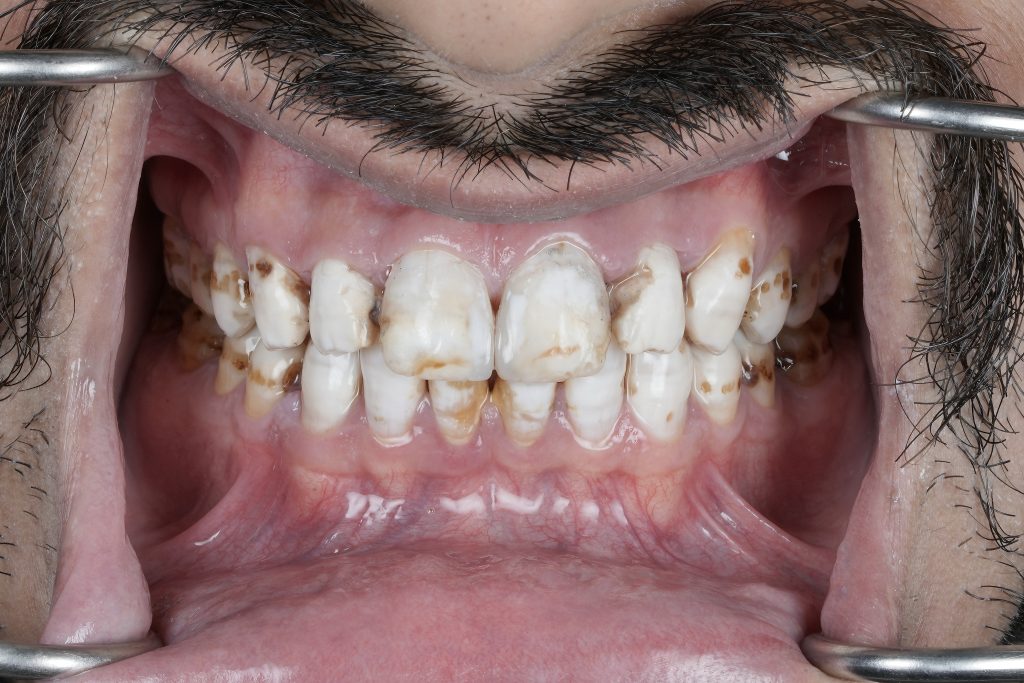

True esthetic dentistry does not begin with restorative materials or ceramic selection. It begins with understanding the condition of the enamel itself. Under proper isolation and magnification, enamel reveals a detailed narrative of demineralisation, developmental defects, discoloration, and marginal compromise that is often masked in routine clinical settings. This article highlights the importance of slowing down, isolating properly, and respecting biological principles to achieve predictable diagnosis, planning, and long-term restorative success.

Modern dentistry often moves fast. Digital workflows, restorative materials, and cosmetic demands can overshadow the most critical diagnostic step: reading the enamel. When teeth are isolated properly and viewed under magnification, enamel becomes a diagnostic map rather than a simple surface.

Demineralised zones, hypoplastic defects, marginal breakdown, and color discrepancies are frequently underestimated when examined without isolation. These subtle findings play a decisive role in treatment planning and directly influence restorative longevity.

This clarity allows the clinician to distinguish between:

- Surface discoloration vs. intrinsic defects

- Active demineralisation vs. arrested lesions

- Hypoplasia vs. wear-related enamel loss